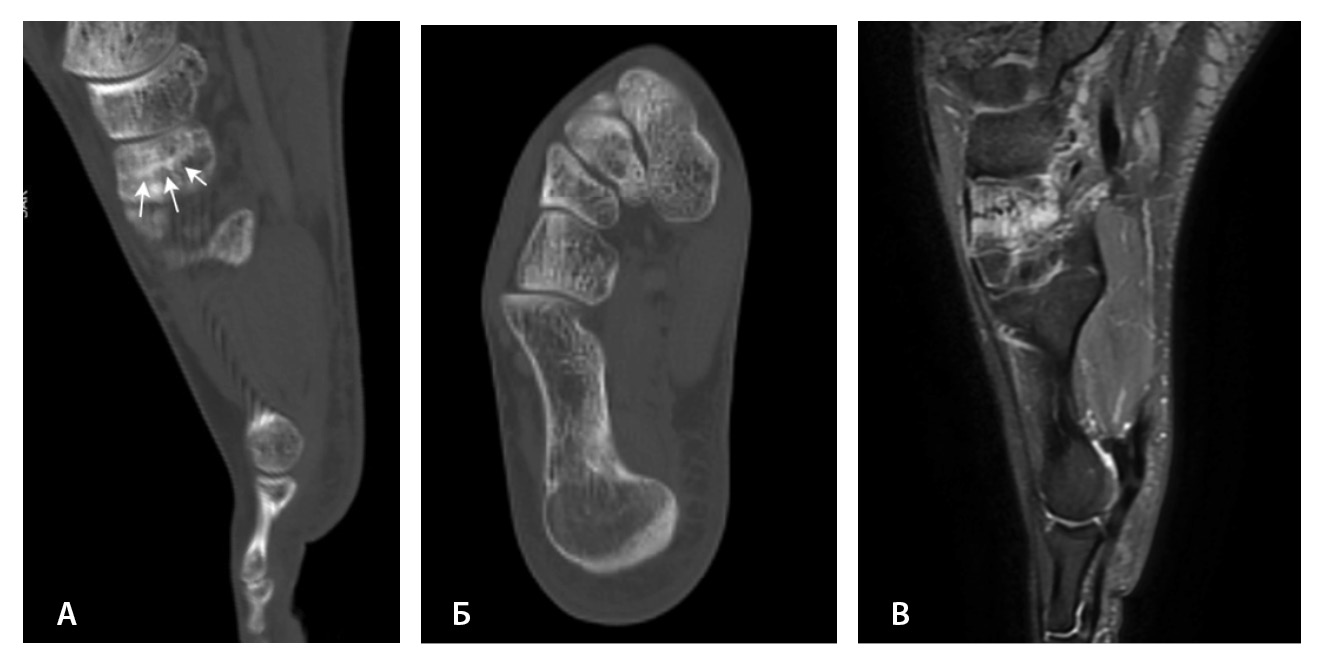

МРТ – наиболее подходящий метод визуализации остеохондрального повреждения купола таранной кости с чувствительностью и специфичностью 96% [52]. В исследованиях M. Haubro и соавт. [53], M. P. Wilson и соавт. [28] МРТ квалифицирована как золотой стандарт диагностики скрытых переломов по сравнению с КТ и рентгенографией. Протокол, состоящий из корональных T1-взвешенных изображений и STIR, обладает 100% чувствительностью в выявлении рентгеннегативных переломов (рис. 3) [28].

МРТ – первоначальный метод диагностики при подозрении на стрессовые переломы, так как ранним признаком таких переломов служит отек костного мозга пораженной кости, ярко выделяющийся среди остальных неизмененных костей. Отсутствие визуализации костного мозга затрудняет диагностику такого рода повреждений при рентгенографии и КТ (рис. 4). Чувствительность МРТ в выявлении стресс-переломов достигает 99% (95–100%), а специфичность – 97% (88–100%). Несмотря на то что исторически сцинтиграфия была основным методом обнаружения стресс-переломов с почти 100% чувствительностью, в настоящее время выполнение радионуклидного метода не рекомендуется из-за его низкой специфичности и высокой дозы ионизирующего излучения [54].